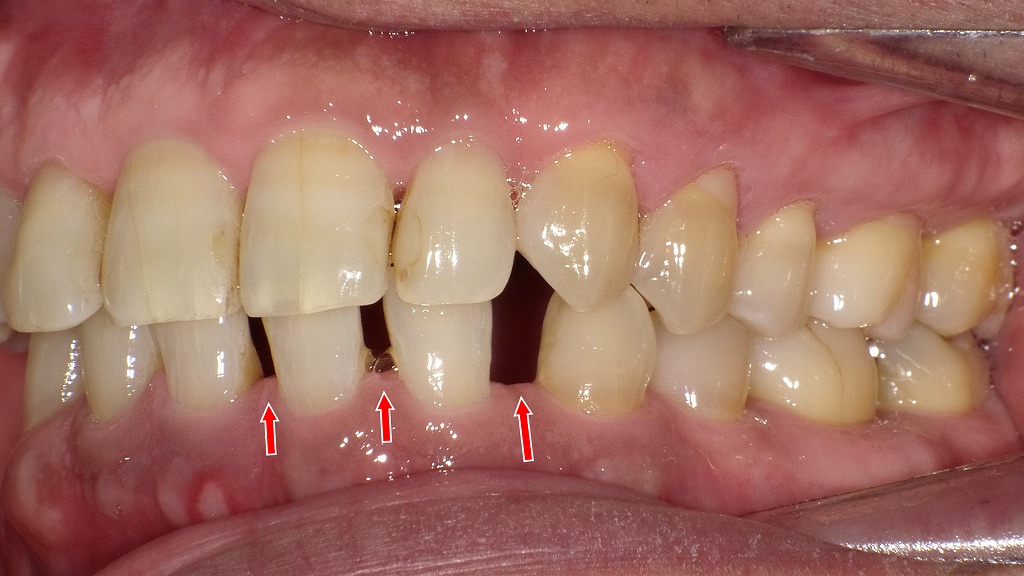

【右側面観と左側面観】

◆ 全体として考えられる影響

- 小臼歯欠損により前歯がすきっ歯のまま安定しやすい

- 噛み合わせのバランスが悪く、長期的には咬耗・歯肉退縮・歯周病リスクも上昇

- 空隙部に食片が入りやすく、清掃性が低下しやすい

- 審美的な問題(前歯の隙間)が日常生活に影響する可能性